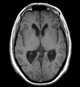

Colloid cyst of third ventricle

A colloid cyst is a non-cancerous tumor in the brain. It consists of a gelatinous material contained within a membrane of epithelial tissue. [Source: Wikipedia ]